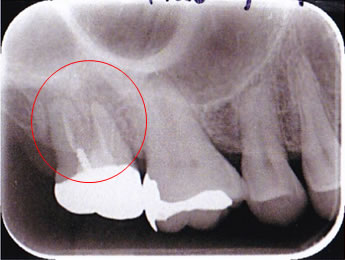

歯科用CT撮影による精密検査

歯科用CTは、X線での断層撮影を行い、コンピューターでのデータ処理・再構成によって、歯や顎骨の状態、神経の位置、血管の位置などを3次元画像で確認できます。

今まで見えなかった病巣や、解らなかった歯の形が鮮明に浮かび上がってきます。顕微鏡との併用により、根管治療の成功率アップに、特に再治療時の診断に大きな貢献をいたします。